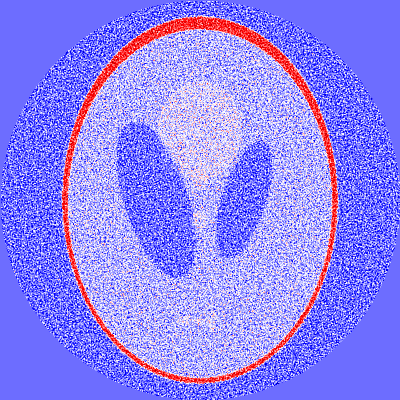

4 Application to X-ray tomography

In this section we apply the concept of filtered DFDs to X-ray tomography as a prime example of an inverse problem in medical image reconstruction. In two spatial dimensions, X-ray tomography can be modeled by the 2D Radon transform. In this section we study filtered DFDs for the Radon transform on L2(2)superscript𝐿2superscript2L^{2}(\mathbb{R}^{2}). Throughout this section, the Fourier transform of a function fL1(n)𝑓superscript𝐿1superscript𝑛f\in L^{1}(\mathbb{R}^{n}) is defined by f(ξ)=nf(x)eiξ,xdx𝑓𝜉subscriptsuperscript𝑛𝑓𝑥superscript𝑒𝑖𝜉𝑥d𝑥\mathcal{F}f(\xi)=\int_{\mathbb{R}^{n}}f(x)e^{-i\langle\xi,x\rangle}\operatorname{d}\!x and extended to functions in L2(n)superscript𝐿2superscript𝑛L^{2}(\mathbb{R}^{n}) by continuity. Its inverse transform is denoted by 1superscript1\mathcal{F}^{-1}. For functions g𝑔g defined on 𝕊1×superscript𝕊1\mathbb{S}^{1}\times\mathbb{R} we write 2gsubscript2𝑔\mathcal{F}_{2}g for the Fourier transform in the second argument.